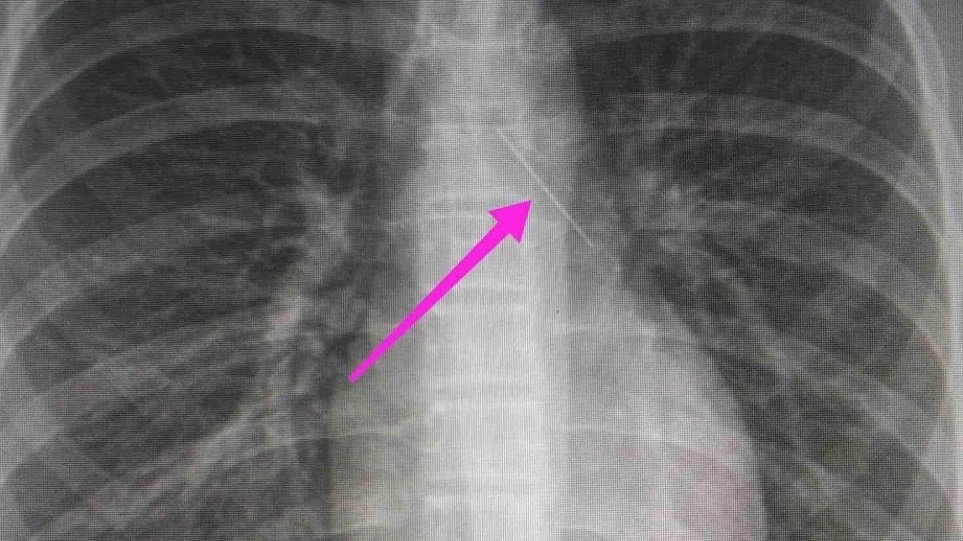

Η ανήλικη υπεβλήθη σε βρογχοσκόπηση και διαπιστώθηκε η μετακίνηση και ενσφήνωση της καρφίτσας στον δεξιό κύριο βρόγχο. Μετά οπό εργώδεις προσπάθειες ολοκληρώθηκε με επιτυχία η αφαίρεσή της.

Κατά την βρογχοσκόπηση διαπιστώθηκε η μετακίνηση και ενσφήνωση του ξένου σώματος στον δεξιό κύριο βρόγχο. Μετά οπό εργώδεις προσπάθειες ολοκληρώθηκε με επιτυχία η αφαίρεση αυτού. Η ασθενής ανένηψε πλήρως εντός της χειρουργικής αίθουσας. Η ασθενής μεταφέρθηκε για παρακολούθηση και νοσηλεία στη Γ’ Παιδιατρική Κλινική.